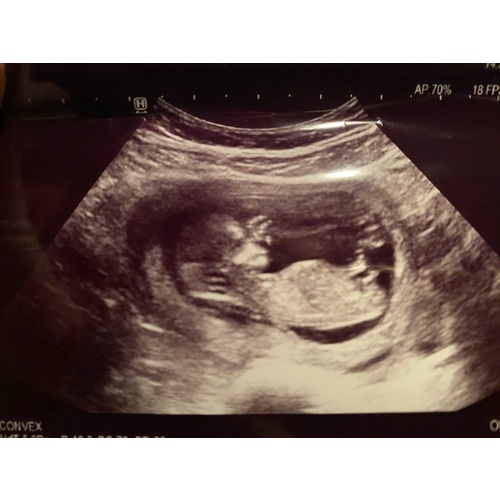

Nee helaas geen meer foto鈥檚. Zit te vergelijken met de andere echo鈥檚 van mi ...

Zover ik kan beoordelen is dit een meisje. Laat je het weten als je geslachtsbepaling hebt gehad? 馃槉

Ga ik zeker doen! Zou eigenlijk volgende week zijn maar nu verzet naar 21 j ...

Nog even geduld dus!